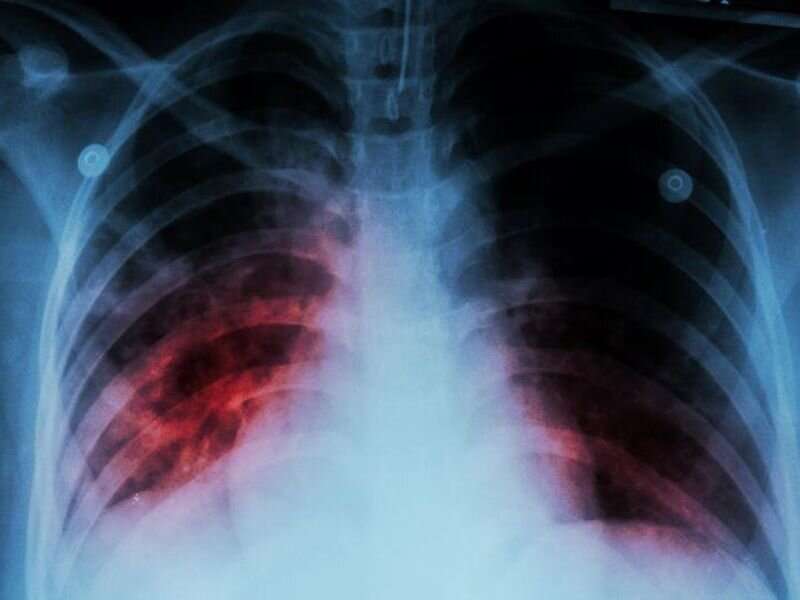

Một ca mắc bệnh lao ở Mỹ - Ảnh: CDC